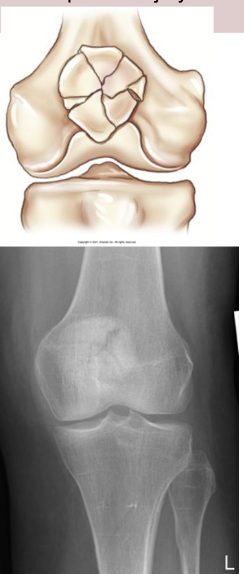

What type of fracture is this?

Segmental - comminuted